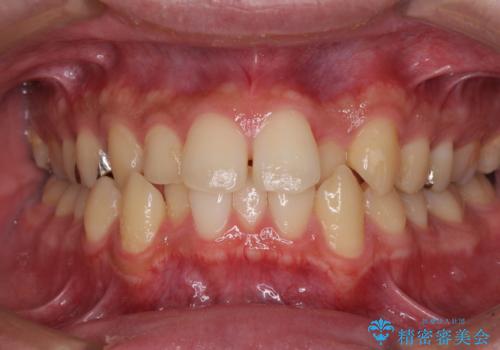

前歯のクロスバイト インビザラインによる矯正治療

- 上下のクロスバイトと前歯のデコボコを気にして来院された患者様です。

インビザラインを用い、IPR(歯と歯の間を削る)と歯列全体を拡大させることで、歯並びを整えていくこととしました。